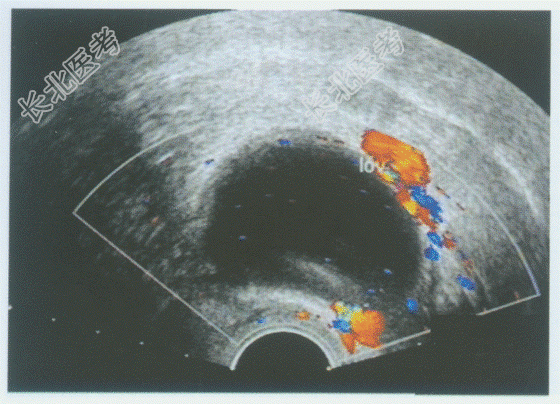

- 单项选择题临床资料:女性患者, 31岁,自述停经45天。

超声综合描述: 经阴道扫查子宫形态饱满,宫腔内可见三个无回声区(图1、图2), 内未见胎芽及胎心搏动。左卵巢内见4.8cm×3.7cm无回声区(图3),边界清晰, 形态规则,CDFI: 周边可见动静脉血流信号(彩图)。

超声提示: A、宫腔积液左卵巢黄体囊肿

B、宫内早孕(三胎)左卵巢黄体囊肿

C、宫内早孕(三胎)左卵巢黄素囊肿

D、葡萄胎左卵巢黄素囊肿

E、宫内早孕(三胎)子宫肌瘤